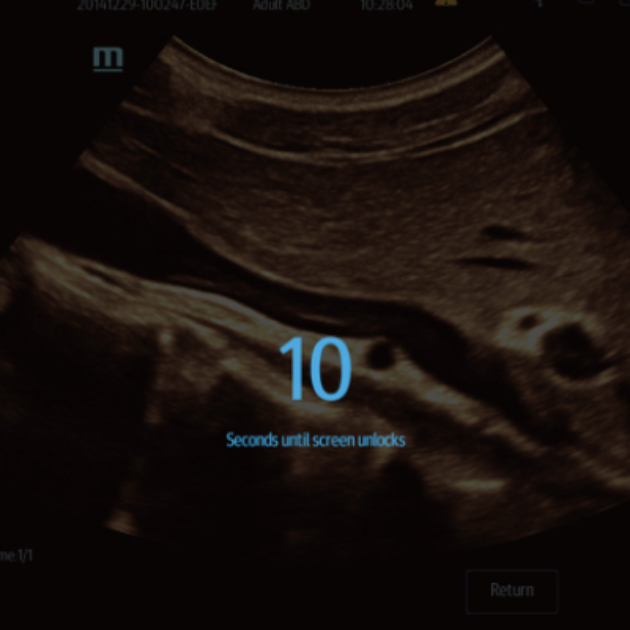

TE7 ACE está equipado con un bloqueo de pantalla único de 10-segundos, que permite a los usuarios limpiar el sistema sin apagar la máquina.